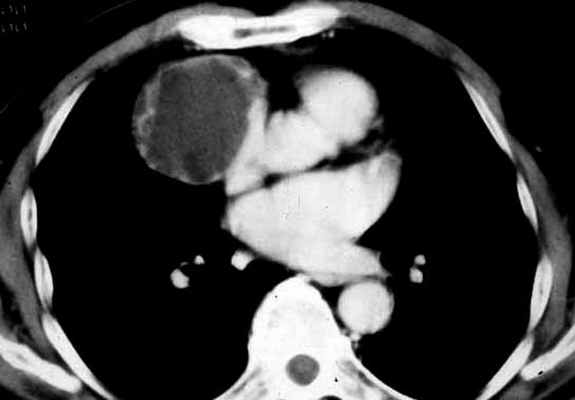

1. Тимомы. Наиболее часто встречающиеся опухоли средостения, составляющие 10-20% всех его новообразований. Для них типична локализация в верхнем отделе переднего средостения (рис. 78), хотя неоднократно описаны тимомы и в других его отделах, что обусловлено аберрантной локализацией тимоцитов.

Рис. 78. Тимома передне-верхнего отдела средостения в виде округлой солитарной опухоли, примыкающей к грудине. Компьютерная томография.

В преобладающем большинстве случаев тимома представляет собой образование округлой или овальной формы (рис. 78), ограниченное фиброзной капсулой неравномерной толщины. Полностью инкапсулированная тимома имеет гладкую или слегка бугристую поверхность. Капсула часто содержит макроскопически заметные